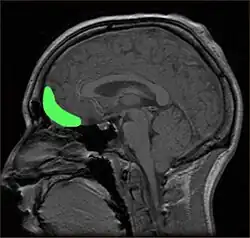

The two main brain structures responsible for impulsivity are the prefrontal cortex and the orbitofrontal cortex. As you read on you will gain a broader understanding into the roles of each specific brain region and how it relates to impulsivity. {{Robelbox|theme=

Prefrontal Cortex: ![]() The prefrontal cortex (PFC) is the frontal lobe's cover found in the outer cortical brain- the cerebrum. The PFC is responsible for thinking, moderating social behaviour, and planning. The PFC consist of two lobes or hemispheres - the right PFC and left PFC - and lies immediately behind the forehead. Together, the two lobes are responsible for many important motivations including affect, goals and personal strivings (Reeve, 2015). The right hemisphere tends to produce negative emotion and no-go avoidance motivation whereas the left hemisphere produces positive emotion and go approach motivation. For example, when thoughts, intentions, goals and strivings stimulate the left hemisphere, a person is likely to generate positive thoughts and approach-oriented feelings. The human PFC is the largest and most evolved of all the primates and continues to develop from infancy right through adolescence and into early adulthood (Hollander & Berlin, 2008). Therefore, its capacity to make complex decisions regarding goals and rewards (as well as the ability put the brakes on behaviour that may lead to adverse outcomes) start off relatively weak during early childhood but grow in strength as the individual matures. |